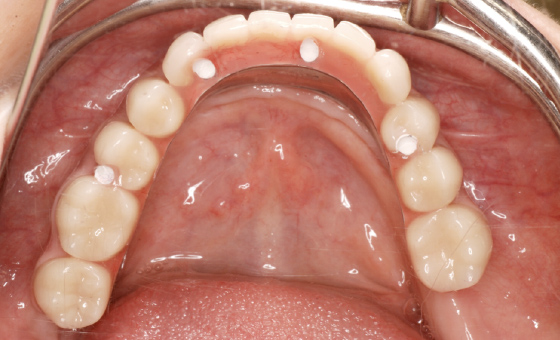

この患者様の場合、治療後半年後のレントゲン写真を見ると、骨とインプラントがしっかりと結合している様子が確認できたので、最終的な人工歯を装着しました。

最終補綴物

人工歯はネジでインプラントに固定してありますので、万が一破損などの場合でも、専用のドライバーで外して修理が可能です。

オールオン4では、失われた歯茎も人工的に作りますので、お口の張りも回復させることができ、自然な美しい笑顔を作ることができます。